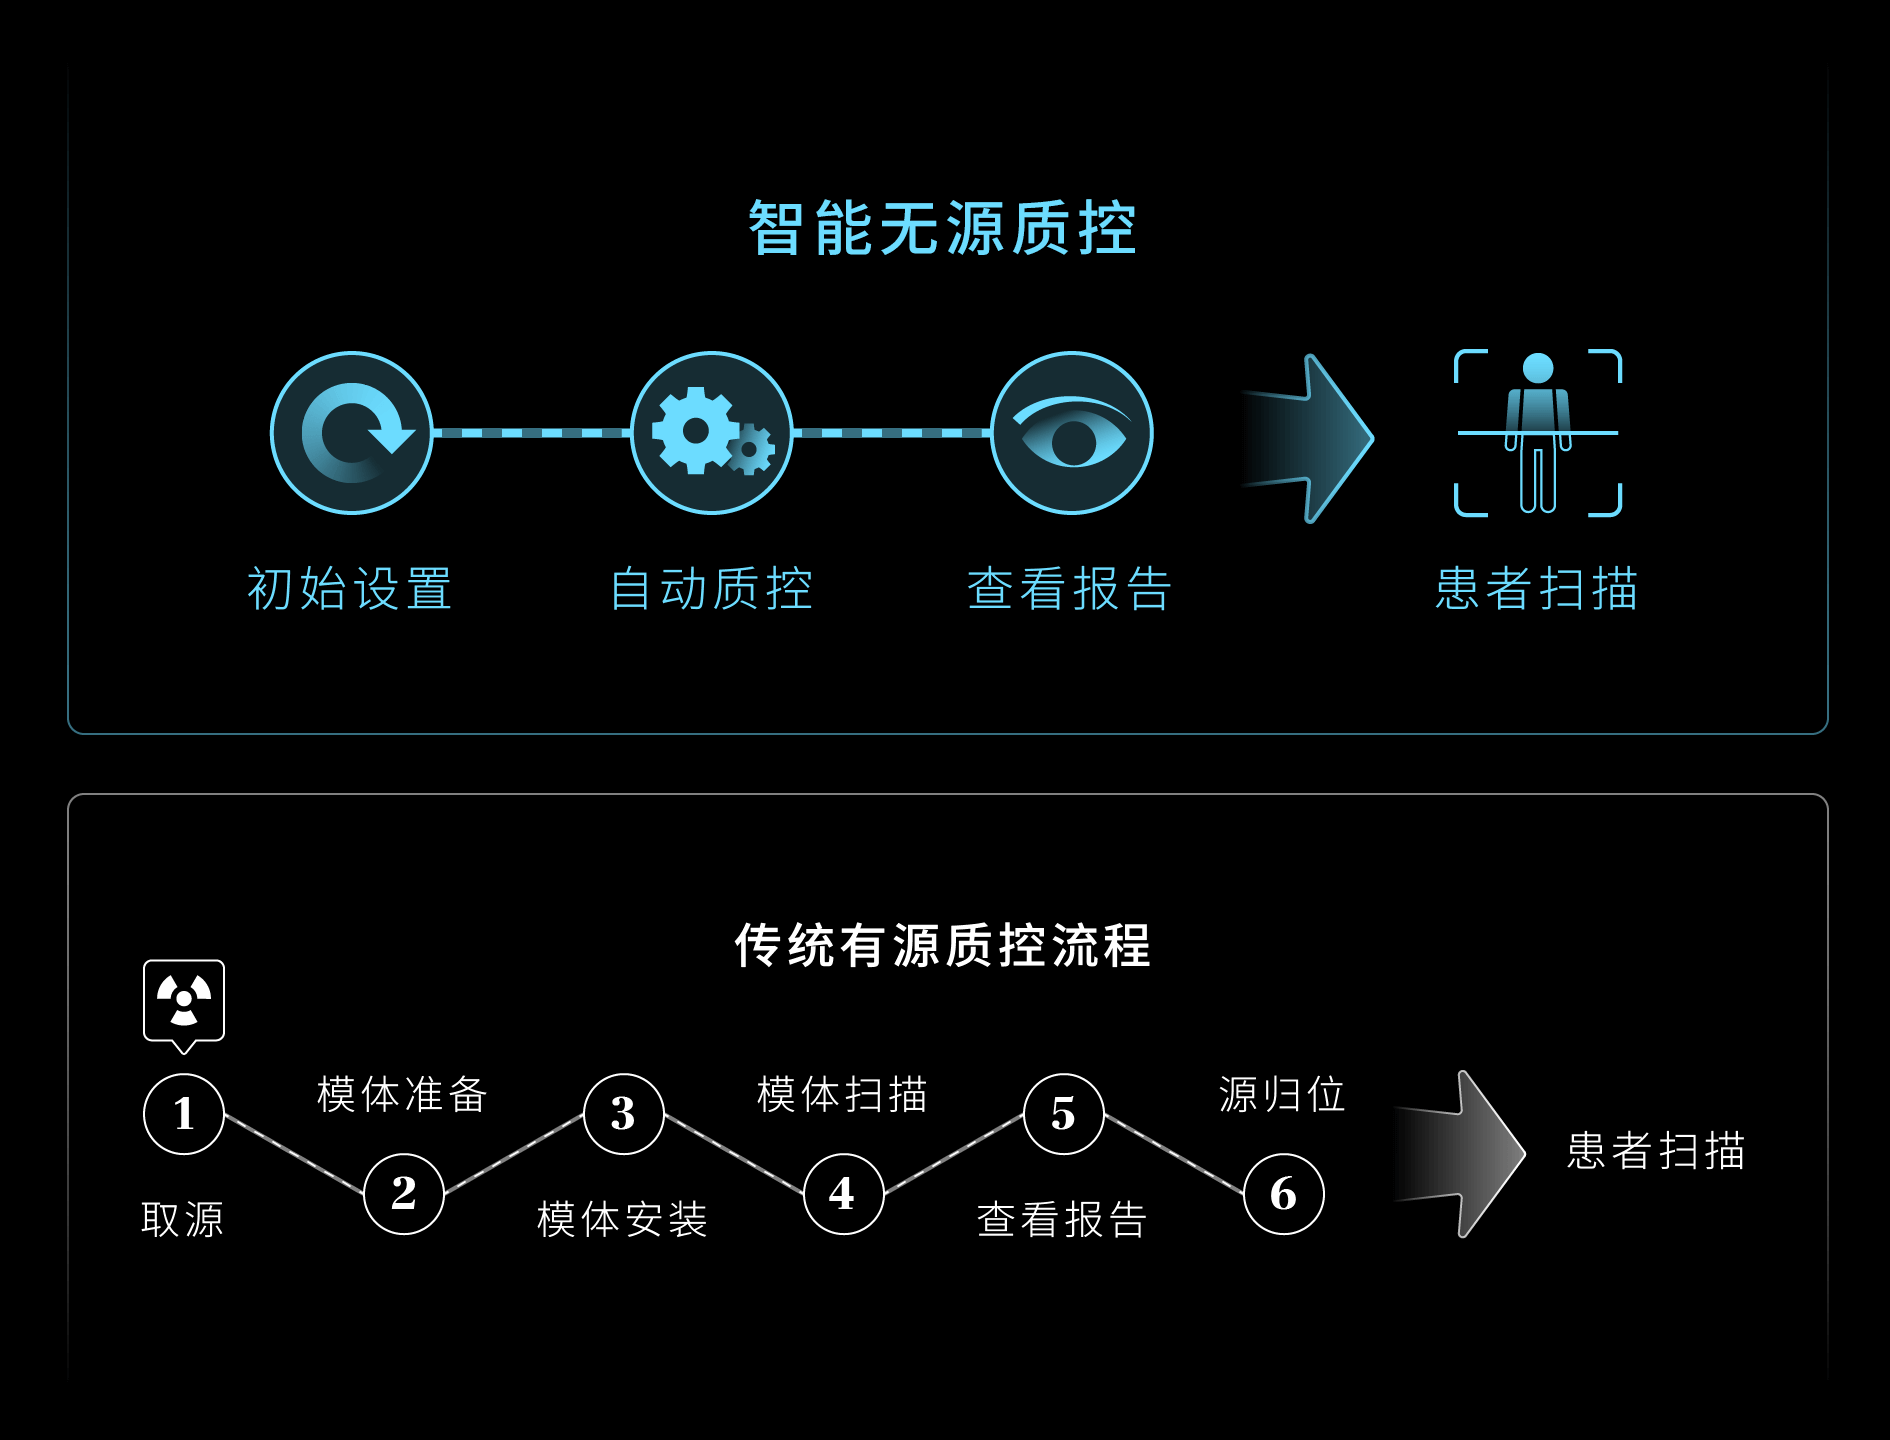

高效运营

智慧绿色质控新体验

自动探测LYSO晶体中176Lu本底符合事件

实现近乎0辐射,免除复杂的有源操作和管理

基于个性化设置自动运行,自动生成质控报告